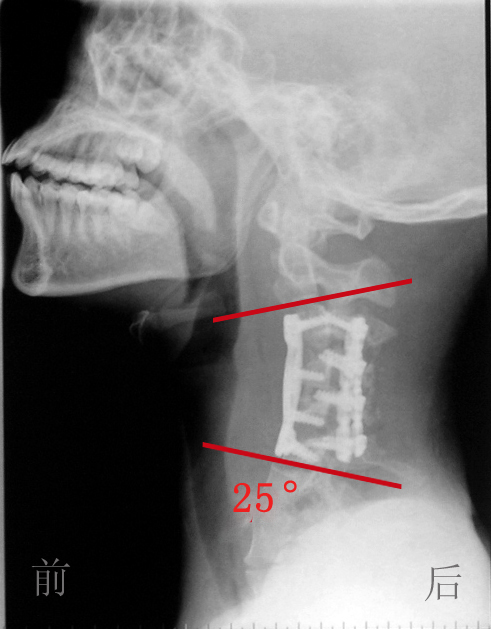

-------125 °颈椎重度后凸畸形奇迹般矫正

最后,治疗小组决定采用循序渐进的策略,采用松解、牵引复位、最后矫形固定的方法。于七月三十一日首先做了一个颈椎前后路联合的充分松解手术;再创新性地采用了一种全新的“平衡悬吊式牵引”方法,在牵引过程中,将项背部悬空,依靠头颅的自身重量,使颈椎后凸的角度逐渐缩小,通过将近4个星期的“平衡悬吊式牵引”,最后拍片发现病人原本125度的颈椎后凸角度已经减少到了25度左右,而且牵引过程中没有出现脊髓损害加重的常见并发症。一个半月后,治疗小组又对其进行了一次颈椎前后路的联合手术,这一次,就用钛板螺钉内固定的手术方法从前后方向将颈椎固定在了最后牵引到达的后凸25度。

术前X线 术后X线